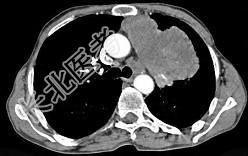

- 单项选择题56岁,男, 意识错乱情绪不稳定一周,请结合胸片和CT, 选出最可能的诊断 ( )

A、肺癌

B、错构瘤

C、胸内甲状腺肿

D、韦格肉芽肿

E、胸腺瘤